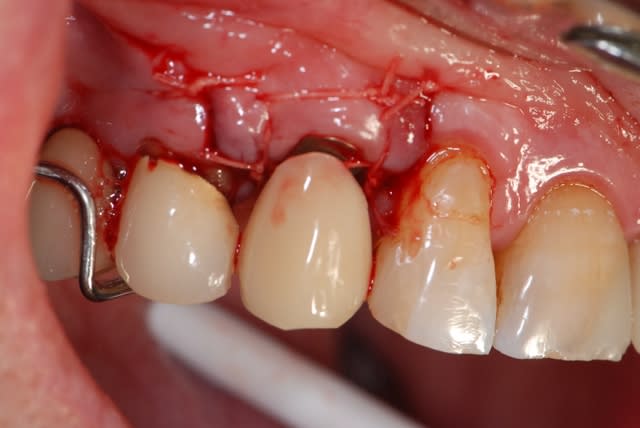

pour candide:

je te propose ce cas que j'ai achevé il y a 2 mois; tu verras que la notion de limite est variable, sauf celle du blocage primaire, d'où cette proposition de mise en esthétique uniquement avec un bon blocage primaire;

dans le cas présenté, je n'ai bien évidemment pas fait de mise en esthétique, j'ai simplement mis une PAP d'une dent, puisque la 14 est une CCM où je ne pouvais pas faire de collage

j'ai mis du ß TCP sans membrane, j'ai eu une très légère récession gingivale que l'utilisation des TBR Zircone autorise sans soucis avec un sourire non gingival

la pose a été faite 6 mois plus tard